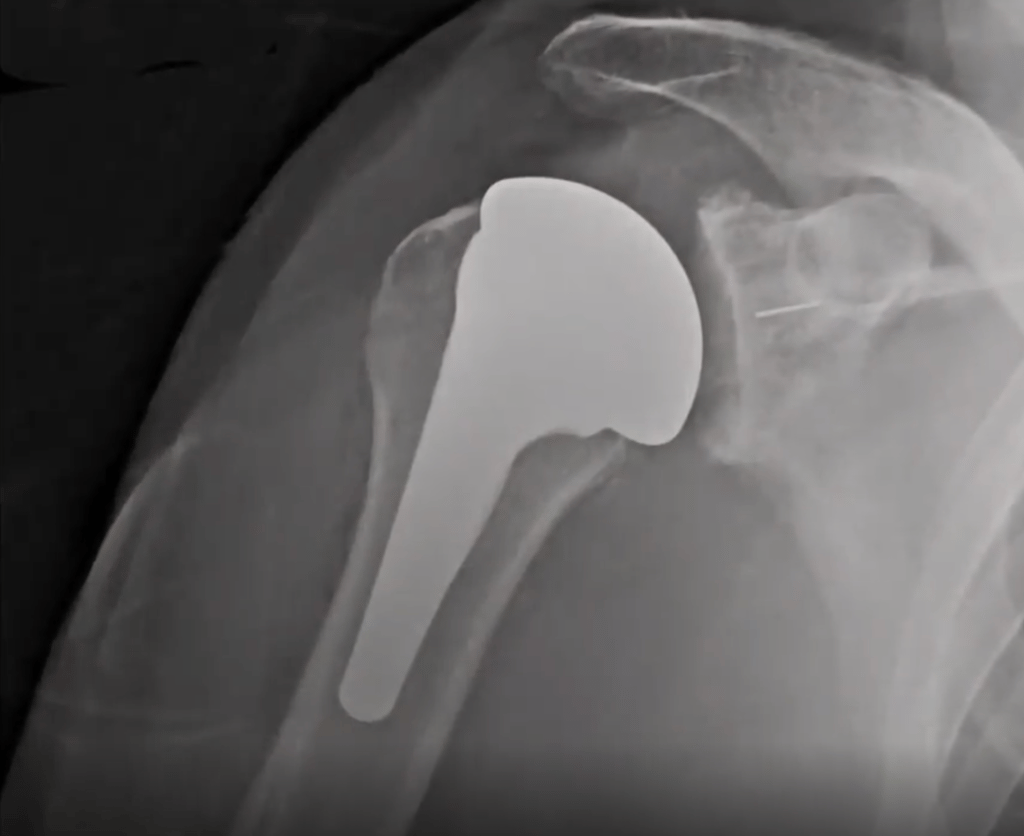

La coiffe des rotateurs étant détériorés, l'action du muscle deltoïde est privilégier pour animer l'épaule. Pour ce faire: les surface articulaire sont inversées:

une sphère est placée sur l'omoplate ( 4)

une cupule est placée au sommet de l'humérus ( 5).

L'intervention nécessite une à deux nuit d'hospitalisation.

La kinésithérapie débute le jour ou le lendemain de l'intervention

Une immobilisation légère de 4 semaines est à respecter hors des séances de kinésithérapie.